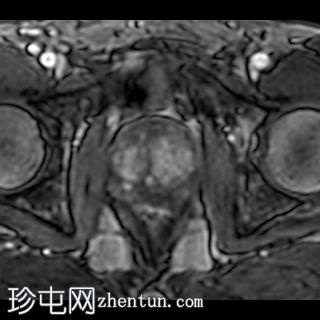

轴位

DWI

在前列腺中部/尖部,右侧外周带/周围膜交界处可见一大小为7 x 5 mm的毛刺状、边界不清的T2低信号病灶,伴有扩散受限和早期动脉期强化,提示为PI-RADS 4级病灶。

一例PI-RADS 4级病变,已安排活检。